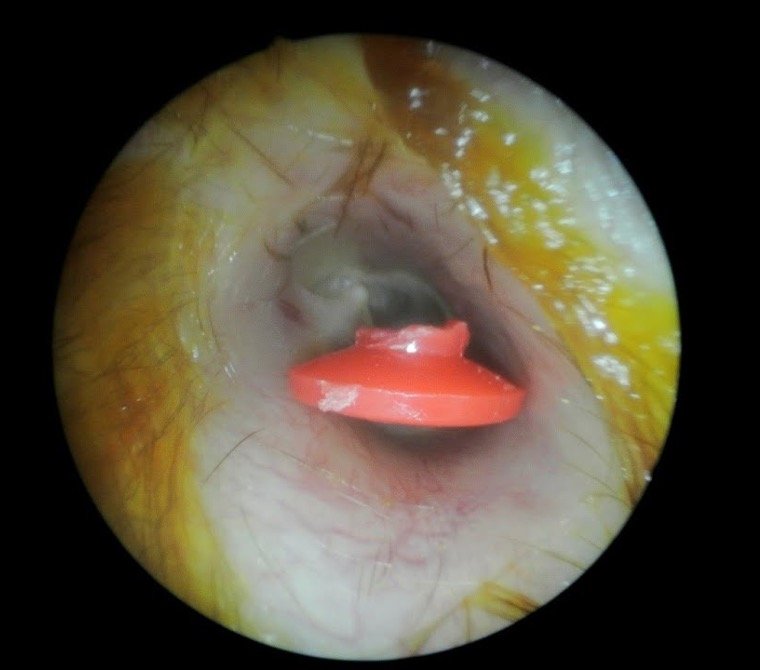

6. Yabancı Cisimler

- Nedenleri: Özellikle çocuklarda, çeşitli nesnelerin kulak kanalına itilmesi.

- Belirtileri: Kulak ağrısı, rahatsızlık, işitme kaybı.

- Tedavi: Yabancı cismin profesyonel olarak çıkarılması.